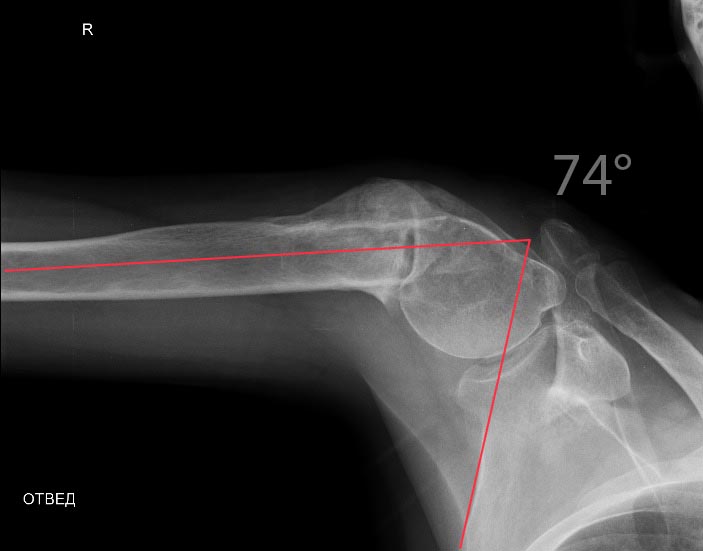

А насчет функции - вот примерчик. До и после коррекции.